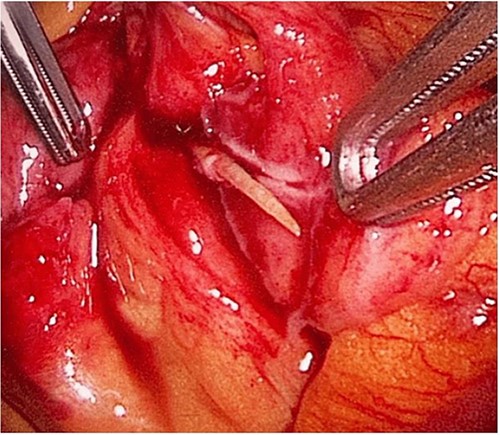

During her hospital stay, the patient showed no improvement regarding abdominal pain, nausea, or abdominal exam. Therefore, she was offered a laparoscopic exploration to verify the diagnosis of a FB to which she agreed. She was taken to the operating room, and the exploration showed an inflammatory process in the LLQ (Fig. 3) with the sigmoid colon attached to the area of the inflammatory reaction. A FB was found in the mesentery of two loops of the ileum 100 cm from the ileocecal junction (Figs 4 and 5). Removal of the FB safely and milking of the small bowel showed no leakage of bowel contents (Fig. 6). And, exploring the rest of the abdomen showed no other pathology and normal ovaries (Figs 7 and 8); the procedure was uneventful. The FB was identified as a toothpick, 3 cm in length (Fig. 9).

The laparoscopic exploration showed the sigmoid colon attached to the area of the inflammatory reaction; straight arrow: site of the toothpick; curved arrow: site of toothpick erosion through the bowel wall; arrowhead: sigmoid colon.

The laparoscopic exploration showed a FB in the mesentery of two loops of the ileum 100 cm from the ileocecal junction—upon partial exposure of the site of the toothpick.

The laparoscopic exploration showed a FB in the mesentery of two loops of the ileum 100 cm from the ileocecal junction—after full exposure of the site of the toothpick.